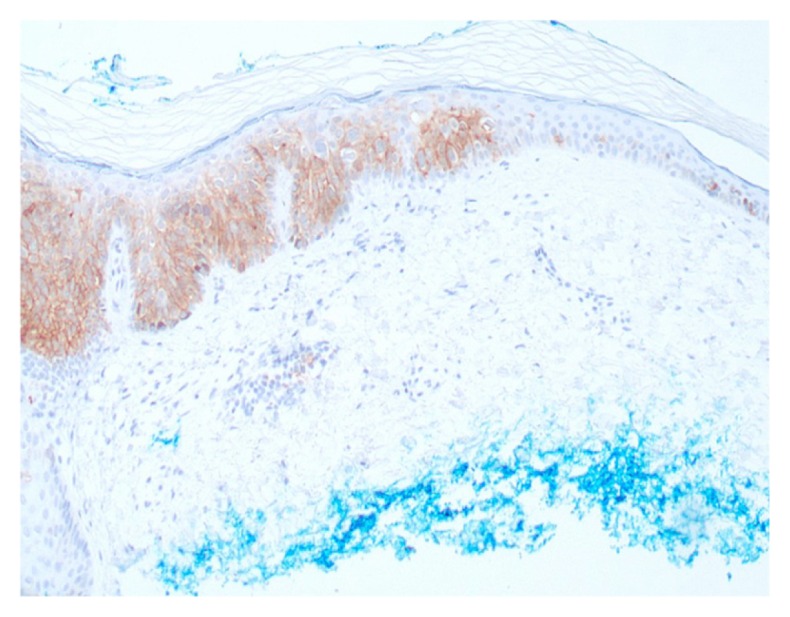

EpCam is a transmembrane epithelial adhesion molecule present on all non-squamous epithelial cells. It is often overexpressed in certain carcinomas, such as breast and colon, and in dermatology, eg, basal cell carcinoma (BCC). Various monoclonal antibodies have been used to detect EpCam, including BerEP4 and epithelial specific antigen. We compared anti-EpCam clones, BerEP4, and epithelial specific antigen clone VU-1D9. One hundred and twelve lesions were stained with both antibodies. All basal cell carcinomas stained uniformly and strongly positive with both antibodies. Diffuse positive staining was also seen in all trichoepitheliomas and merkel cell carcinomas. Focal positive staining was seen in squamous cell carcinoma and benign sebaceous neoplasms. Clone VU-1D9 was more likely to produce focal positive staining as compared to BerEP4. This focal positive staining of sebaceous neoplasms and squamous cell carcinomas is a potential diagnostic pitfall.